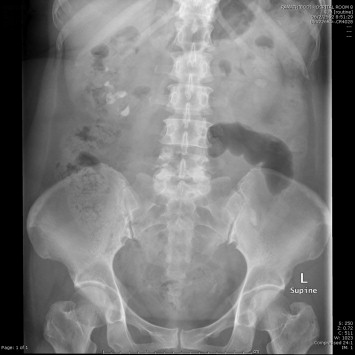

The left caliceal stone was disintegrated completely by extracorporeal shockwave lithotripsy. One month later, PCNL was performed on the right staghorn calculi and the upper caliceal branch of the lower moiety was clearly removed. The removal of the lower caliceal branch and the rest failed because the access tract was lost and there was also a thinning cortex (Fig. 3). The residual stones were later removed by single port laparoscopic nephrolithotomy using an R-port via an umbilical incision.

Residual stone at lower moiety after percutaneous nephrolithotomy.

Figure 3.